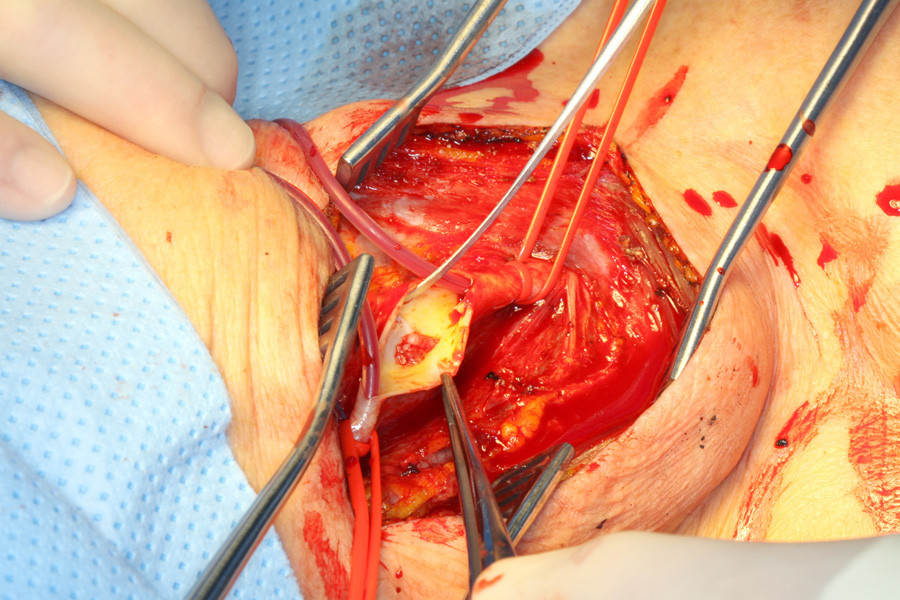

Det ble gjort carotiskirurgi med ekstirpasjon av en gelatinøs stilket, fluktuerende masse (bilde kun i nettutgaven), som ved mikroskopisk undersøkelse var dominert av fibroblaster, ikke lipider eller kalk som ved aterosklerotiske plakk. Flere måneder postoperativt er pasienten fri for nye iskemiske hendelser.